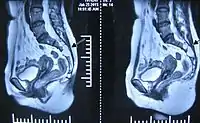

影像学检查

CT可以观察骶管囊肿所引起的骨质侵蚀,但不如磁共振显示囊肿清晰。磁共振是检查骶管囊肿的主要手段,磁共振T2相可以清楚地分辨骶管囊肿的位置、大小、与硬脊膜囊的关系、与神经根的关系等。